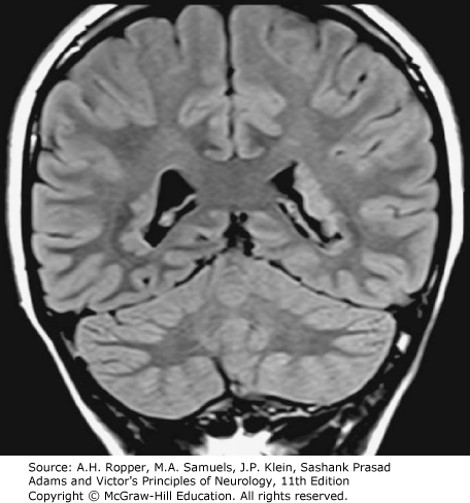

Focal cortical dysplasia. A T2-FLAIR MRI in the coronal plane in a patient with seizures. Deep in the white matter, adjacent to the lateral ventricles, are multifocal heterotopic aggregates of gray matter, more apparent in the left hemisphere.

Source: Ropper AH, Samuels MA, Klein JP, Prasad S. Adams and Victor's Principles of Neurology, 11e; 2019.